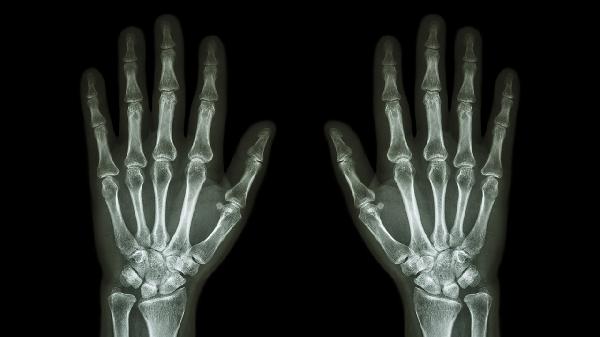

手指关节疼痛肿胀僵硬怎么治疗

手指关节疼痛肿胀僵硬可通过生活调理、物理治疗、药物治疗、手术治疗等方式治疗。手指关节疼痛肿胀僵硬可能由关节劳损、骨关节炎、类风湿关节炎、痛风性关节炎、感染性关节炎等原因引起。

保持手指关节健康需要建立科学的生活习惯。日常注意手部保暖,避免长时间接触冷水。工作时定期做手指操放松,使用符合人体工学的工具减轻关节压力。均衡摄入优质蛋白和抗氧化营养素,适量进行握力训练维持关节稳定性。若症状持续加重或出现关节变形,应及时到风湿免疫科或骨科就诊,通过血液检查、影像学检查明确诊断。治疗期间严格遵循医嘱,不自行调整药物剂量,定期复查评估治疗效果。良好的关节护理结合规范治疗能有效控制病情发展,提高生活质量。